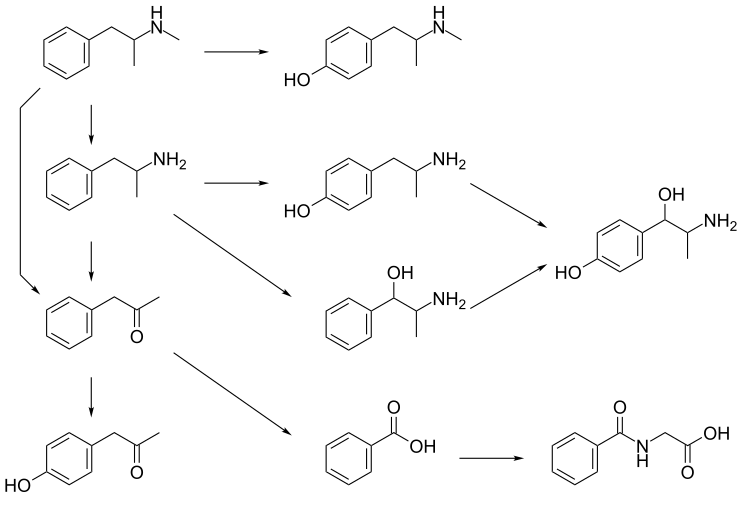

CYP2D6, dopamine β-hydroxylase, flavin-containing monooxygenase 3, butyrate-CoA ligase, and glycine N-acyltransferase are the enzymes known to metabolize methamphetamine or its metabolites in humans.[sources 2] The primary metabolites are amphetamine and 4-hydroxymethamphetamine;[132] other minor metabolites include: 4-hydroxyamphetamine, 4-hydroxynorephedrine, 4-hydroxyphenylacetone, benzoic acid, hippuric acid, norephedrine, and phenylacetone, the metabolites of amphetamine.[9][132][133] Among these metabolites, the active sympathomimetics are amphetamine, 4‑hydroxyamphetamine,[139] 4‑hydroxynorephedrine,[140] 4-hydroxymethamphetamine,[132] and norephedrine.[141] Methamphetamine is a CYP2D6 inhibitor.[115]

The main metabolic pathways involve aromatic para-hydroxylation, aliphatic alpha- and beta-hydroxylation, N-oxidation, N-dealkylation, and deamination.[9][132][142] The known metabolic pathways include:

Metabolic pathways of methamphetamine in humans[sources 2]